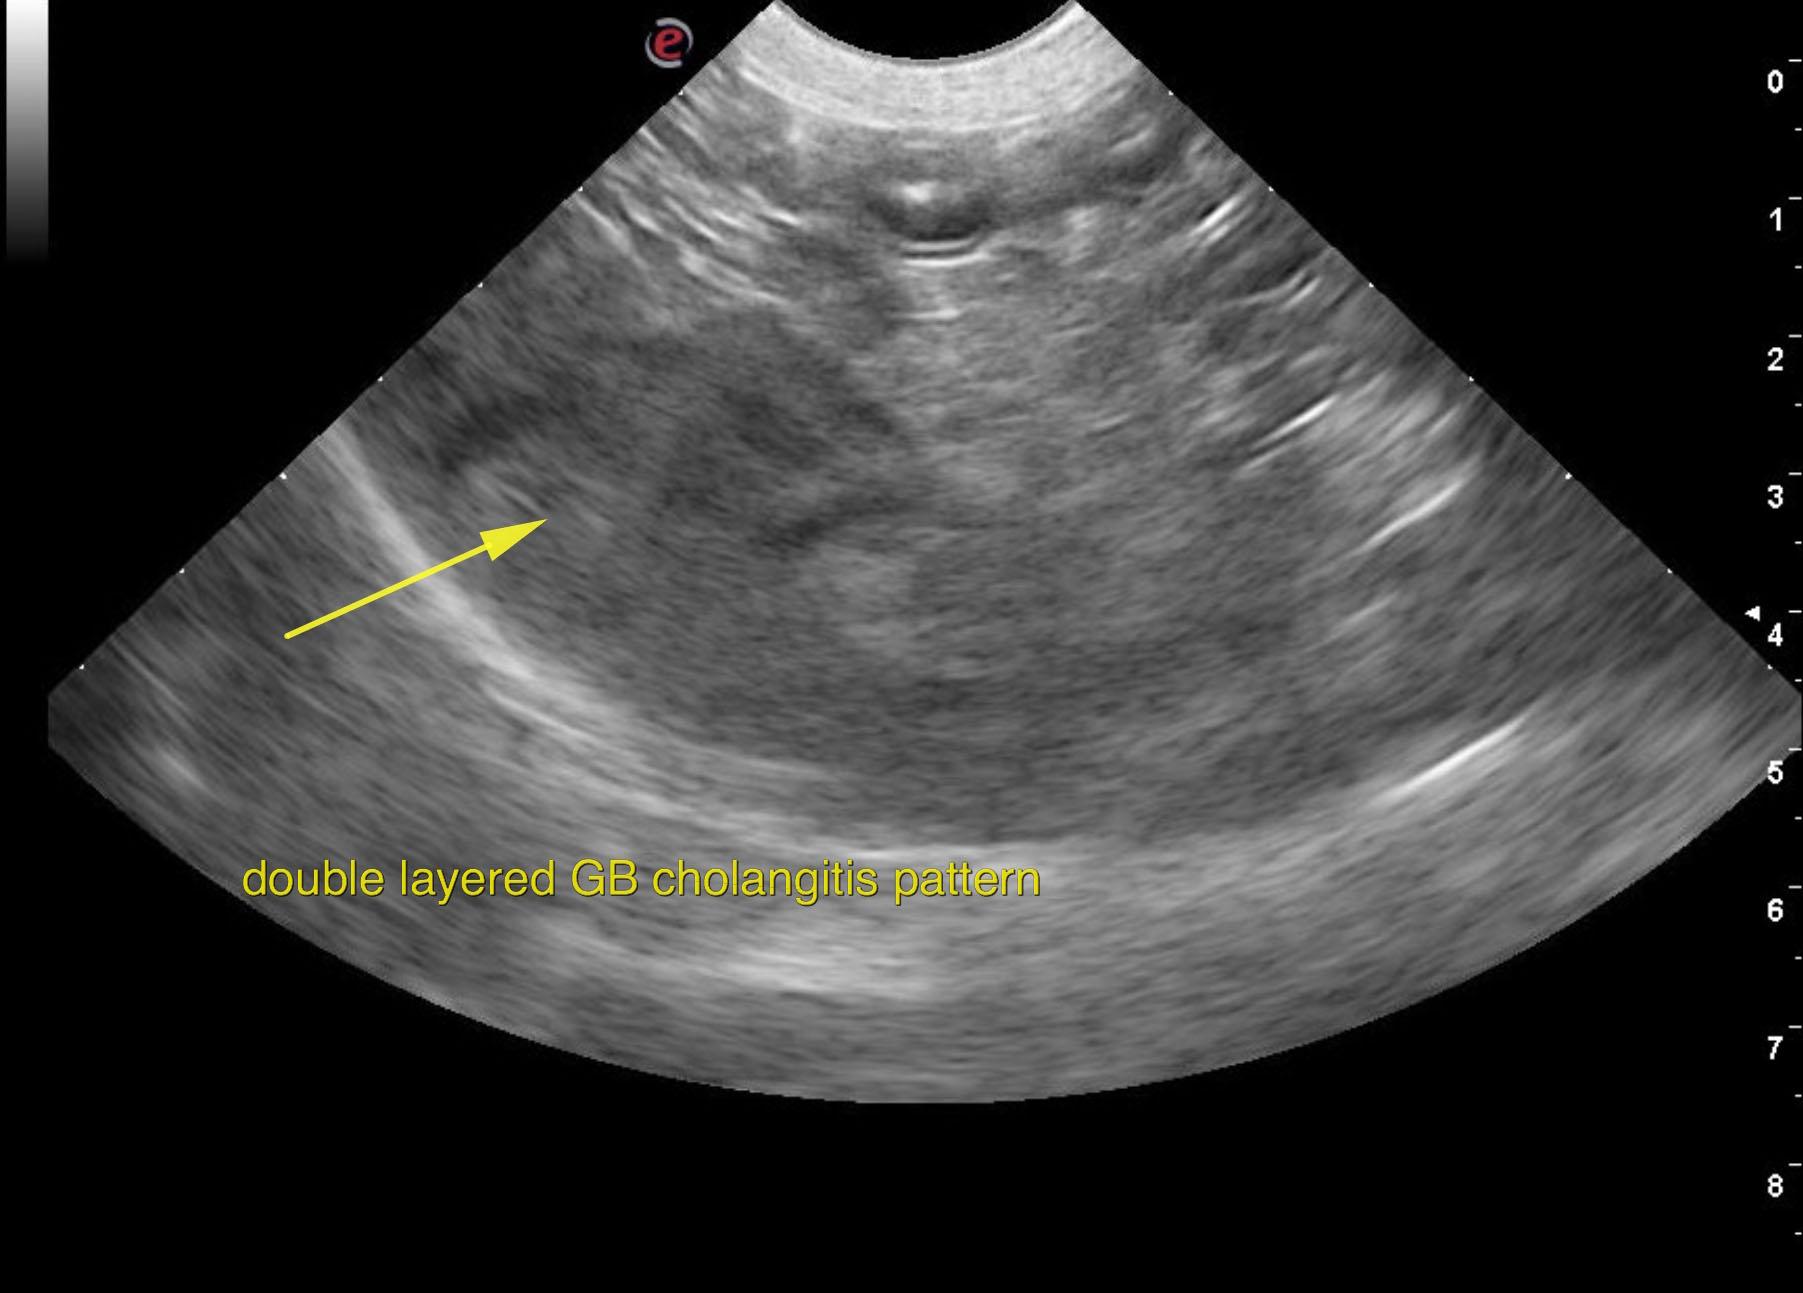

A 7-year-old female Beagle with a history of reduced appetite for a few days was presented for evaluation vomiting and hemorrhagic diarrhea. On physical examination, icterus was present. Urinalysis showed specific gravity of 1.004, bilirubinuria, and hematuria. Abnormalities on serum biochemistry were severely elevated ALT (1247) and ALP (1057) activity and bilirubin (11.9) and low BUN. CBC and radiographs were both within normal limits.